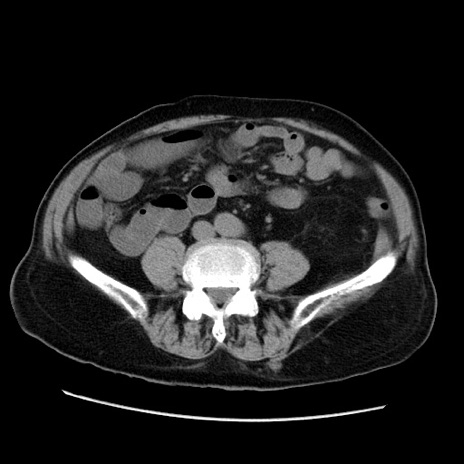

症例21(横断像)

【症例】70歳代男性

【主訴】腹痛

【現病歴】肝硬変・肝細胞癌にてかかりつけの方。約9時間前に食後より腹痛出現。症状が徐々に増悪し、嘔吐出現したため来院。

【既往歴】肝硬変、肝細胞癌(RFA、TACE後)

【身体所見】意識清明、表情苦悶様、BT 36℃、BP 129/78mmHg、P 88bpm、SpO2 97%(RA)、右上腹部から心窩部にかけて圧痛あり、反跳痛なし、筋性防御あり。

【データ】WBC 5800、CRP 0.16